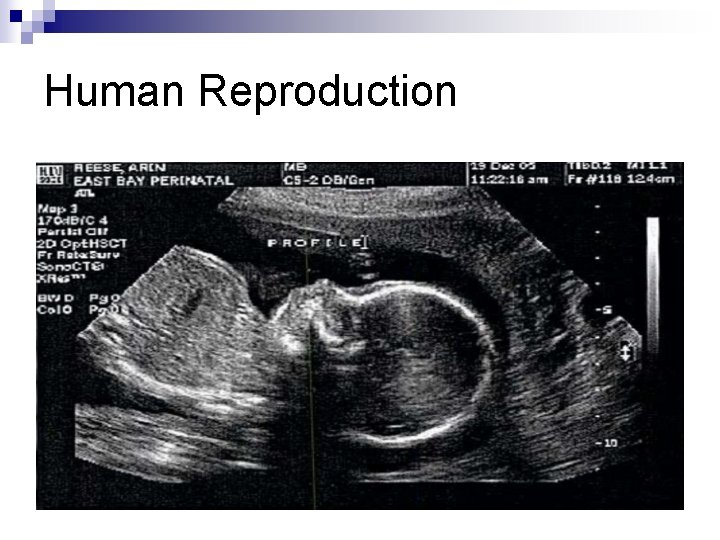

Human Reproduction n Sonogram- The picture of the fetus produced by an ultrasound screening. ¨ Can determine position of the baby, any abnormalities, and often the sex.